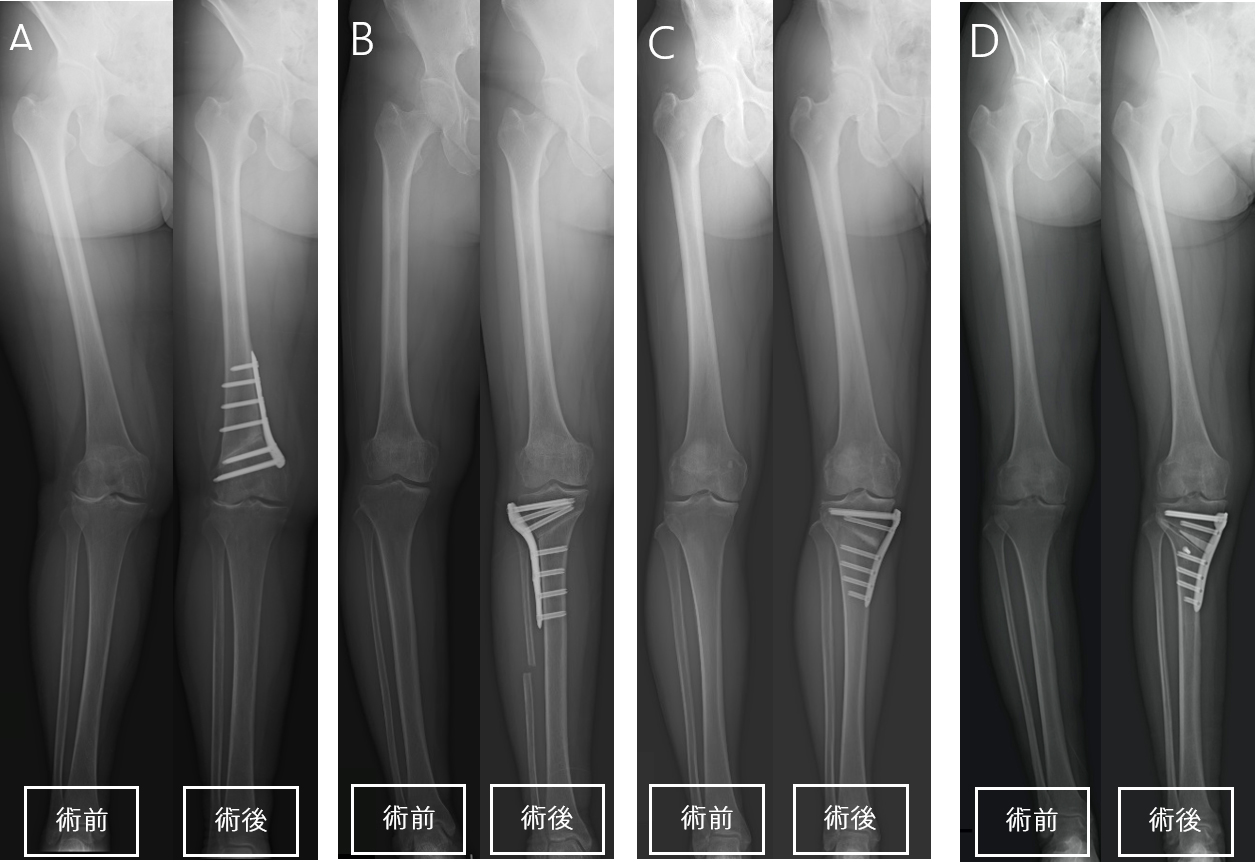

・大腿骨遠位骨切り術(DFO:Distal Femoral Osteotomy):(図2)

【図2 DFOの骨切り位置】

大腿骨と呼ばれるふとももの骨を膝に近い位置で切り、変形を矯正する手術になります。大腿骨を楔状に切り落として変形を矯正することがほとんどです。

・脛骨高位骨切り術(HTO:Hight Tibial Osteotomy):(図3)

【図3】

左はOpen Wedge HTOおよびDTOの骨切り位置

右はHybrid Closed Wedge HTOの骨切り位置

脛骨と呼ばれるすねの骨を膝に近い位置で切り、変形を矯正する手術になります。HTOにはOpen Wedge HTOとHybrid Closed Wedge HTOがあります。Open Wedge HTOは、内側から外側に向かって脛骨を切り、人工骨を入れて変形を矯正する方法になります。Hybrid Closed Wedge HTOは、外側から内側に向かって脛骨を楔状に切り落として、変形を矯正する方法になります。Hybrid Closed Wedge HTOの場合、腓骨と呼ばれる脛骨に並走する骨も切り落とします。どちらの方法を用いるのかは、変形の程度によって選択されます。

・脛骨遠位粗面下骨切り術(DTO:Distal Tuberosity Osteotomy):(図4)

【図4】

左はOpen Wedge HTOの骨切り位置

右はDTOの骨切り位置

基本的にはOpen Wedge HTOと同様の手術になります。Open Wedge HTOの場合、脛骨粗面と呼ばれる膝蓋腱の付着部を遠位側に残すように骨切りされます。近年、この手術によって膝蓋骨の位置が変化することで、膝蓋大腿関節における関節症の発症リスクが高まる可能性が示されています。この解決策として誕生したのがDTOになります。DTOは従来のOpen Wedge HTOにおける脛骨粗面の骨切り方法を変更したものです。脛骨粗面を近位側に残すよう骨切りすることで、膝蓋骨の位置が変化せず、膝蓋大腿関節における関節症の発症予防になると考えられています。

一般的に、変形膝関節症による内反変形に対してはHTOまたはDTOが用いられ、外反変形に対してはDFOが用いられます(図5)。また、変形が高度の場合は、DLO(Double Level Osteotomy)と呼ばれる大腿骨と脛骨の両方の骨切りを行う手術も用いられます。

骨切り術の適応としては、骨粗鬆症がないことに加え、年齢や変形の程度、靭帯損傷の有無などが考慮されます。

【図5 各術式の手術前後のX線(下肢全長)。AはDFO、BはHybrid Closed Wedge HTO、CはOpen Wedge HTO、DはDTO。

DTOは脛骨粗面を固定するスクリューを使用するため、Open Wedge HTOにはないスクリューがX線で確認できます。】